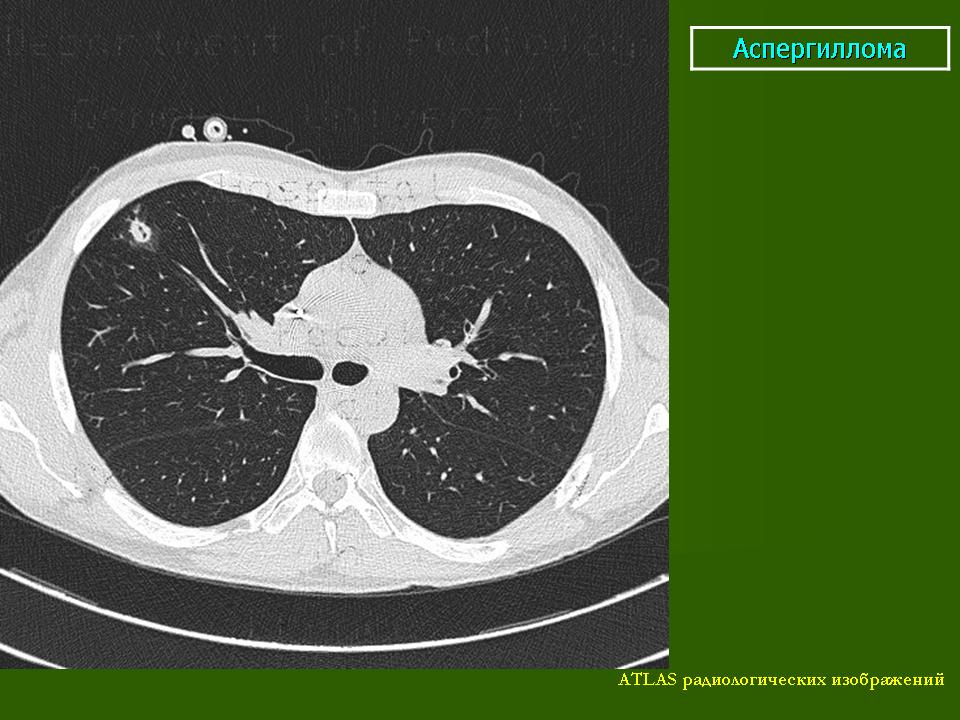

При вдыхании спор возникает первичная инфекция, при которой наблюдаются изменения в легких. Иногда микробы могут проникнуть через кожу. Первичная инфекция легких обычно протекает бессимптомно. Клинические симптомы развиваются только в 30% случаев и инфекция диагносцируется на основании положительной кожной реакции с кокцидиоидином. При рентгенологическом исследовании можно обнаружить только нежные затемнения в области гилюсов. Изменения эти исчезают в течение 1-2 недель. Чаще всего наблюдаются воспалительные инфильтраты, которые при рентгенологическом исследовании представляются в виде мягких однородных затемнений, распространяющиеся от гилюса в нижние и средние легочные поля. Чаще всего такие затемнения исчезают в течение 1-2 недель.

Для легких характерны инфильтраты, имеющие диаметр 2-3 см и нередко располагающиеся в средних и нижних легочных полях. Чаще всего инфильтраты в легких бывают единичные, но бывают и множественные, напоминающие метастазы или первичный туберкулез. Очаги имеют спокойный характер, через несколько месяцев рассасываются или распадаются, образуя тонкостенные полости.

При кокцидиоидомикозе увеличение медиастинальных и гилюсных лимфатических узлов бывает не часто и, обычно связано с инфильтрацией легочной ткани при остром течении болезни. Иногда наблюдается небольшой экссудат, располагающийся в ребернодиафрагмальном синусе, который быстро всасывается. Большие экссудаты бывают редко.